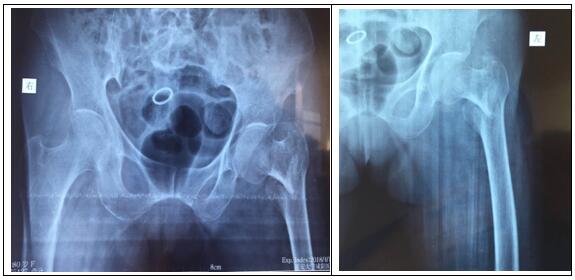

患者房某,80歲,女。因摔傷致左髖部疼痛,左下肢負(fù)重功能障礙,由外院轉(zhuǎn)入我院骨一科。確診為:左側(cè)股骨轉(zhuǎn)子間骨折。

圖片一:(術(shù)前照片)